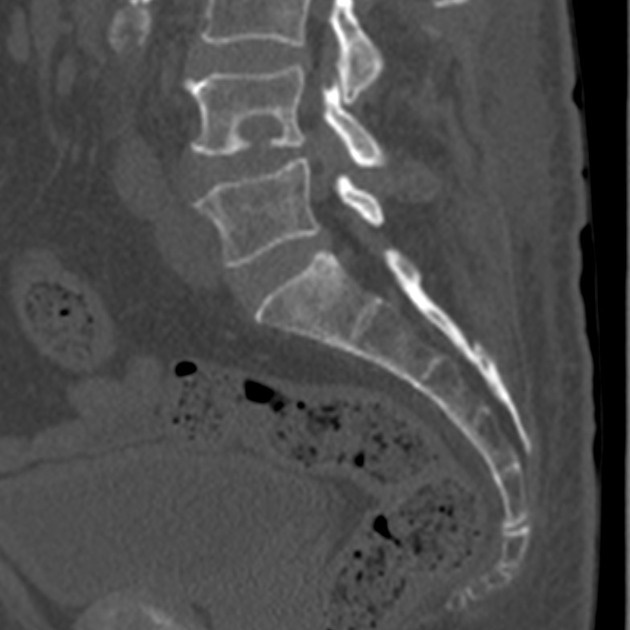

Transverse (horizontal) and coronal cross sections retrieved from the µCT scans of the large (a,b) and small (c,d) vertebrae. In some areas, there is clear evidence of bone remodeling adjacent to the tumor (sclerotic margins). Multiple lesions coalesce, thus creating a single lesion with well-circumscribed margins, having the “geographic” pattern (a term applied to a meandering border).